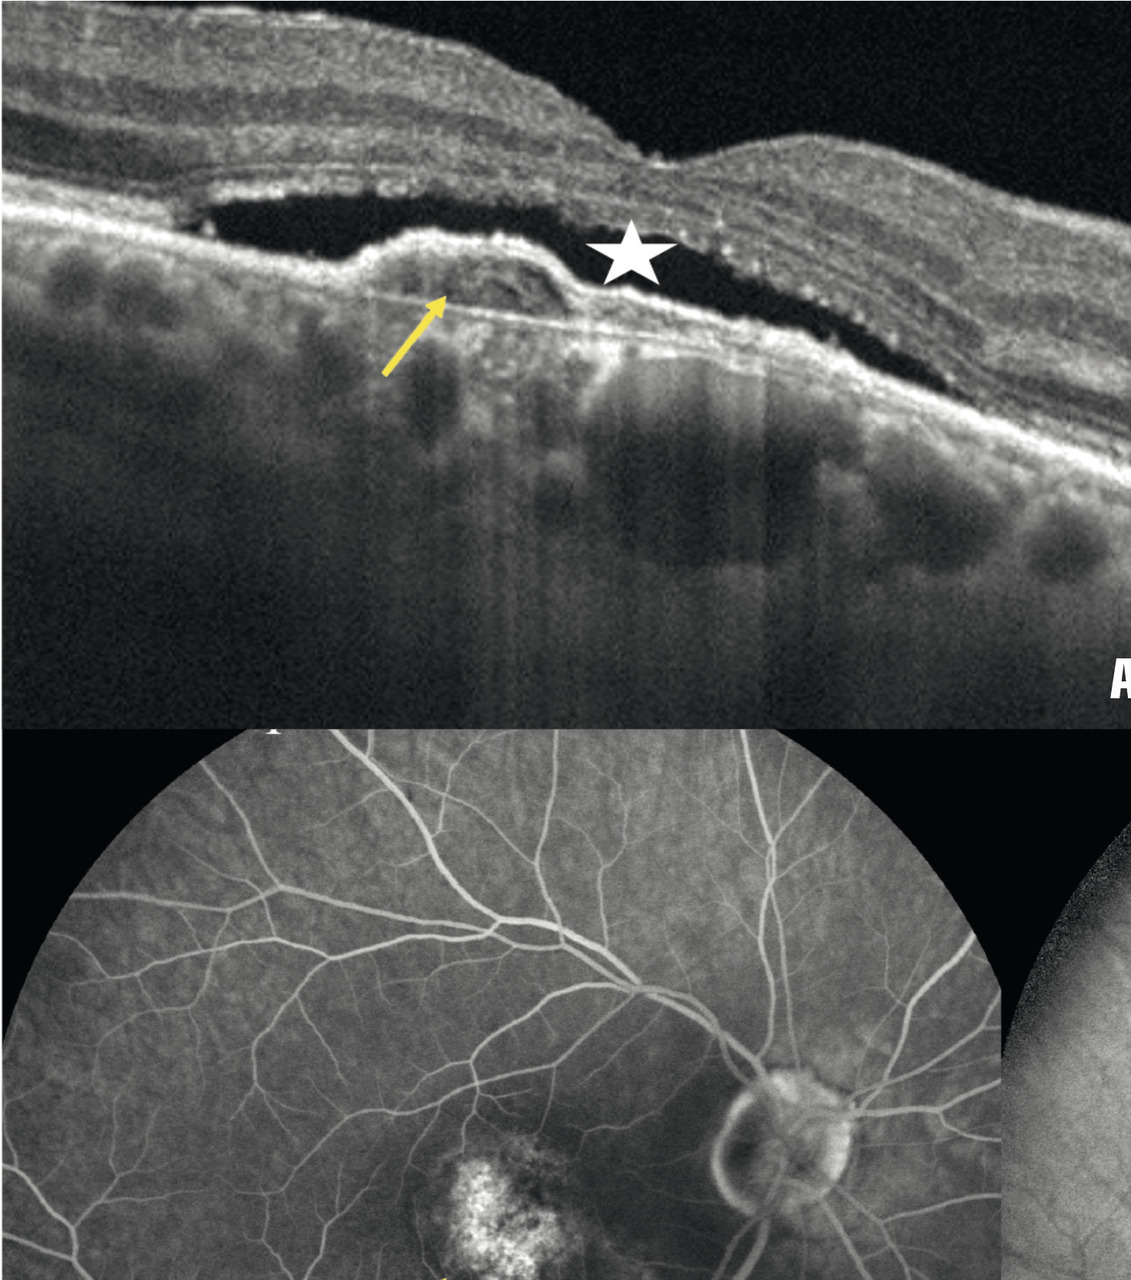

Dans la DMLA exsudative, les néovaisseaux sont visibles comme des lésions fusiformes hyper- réflectives, ainsi que leur activité : décollement séreux rétinien et logettes d’œdème intrarétiniennes (fig. 5 ).

Commercialisé en 2015, cet examen prend une place grandissante. L’appareil utilise une technique dérivée de l’OCT qui mesure la vitesse des hématies et donne des images non invasives du flux vasculaire. Il est particulièrement intéressant dans la forme exsudative, en montrant les néovaisseaux choroïdiens sans nécessiter l’injection de produits de contraste (fig. 5 ). L’association à l’OCT classique permet de visualiser leur activité (DSR, œdème). à l’avenir, il est possible que l’angio-OCT se substitue à l’angiographie à la fluorescéine pour le diagnostic de DMLA exsudative.

Historiquement, l’angiographie à la fluorescéine est le gold standard du diagnostic et du suivi des DMLA exsudatives. Des photos du fond d’œil sont réalisées après injection d’un colorant fluorescent par voie intraveineuse. Il révèle les vaisseaux rétiniens et les signes indirects de perméabilité des néovaisseaux choroïdiens. On peut lui associer le vert d’indocyanine en cas de doute diagnostique ou de forme particulière de DMLA (fig. 5 ). Toutefois, des réactions d’hypersensibilité ont été rapportées avec la fluorescéine : chocs anaphylactiques qui ont parfois conduit au décès des patients. Ce risque impose un interrogatoire précis et une éventuelle prémédication anti-allergique. L’intérêt de l’examen est donc de plus en plus discuté. L’angio-OCT, indiqué en 2e intention en cas de doute diagnostique, pourrait le détrôner.